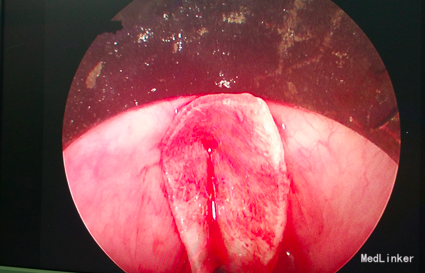

入院诊断:声带粘连 治疗:入院后全麻下行声带粘连部二氧化碳激光切除,局部安放喉膜,术后观察一周,术后三周去除喉膜。